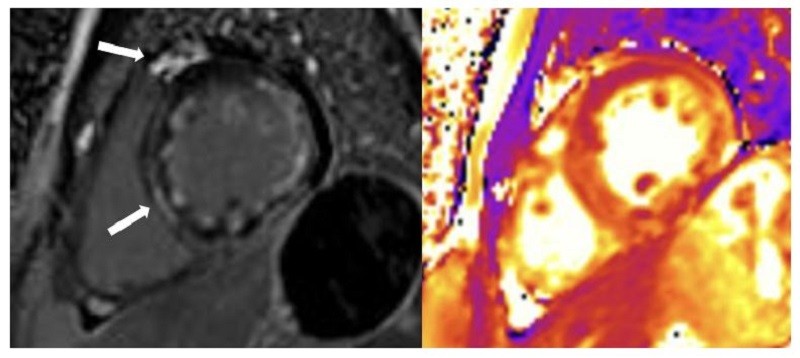

Hình cộng hưởng từ tim của anh L.V.H ghi nhận nhận nhiều tín hiệu viêm cơ tim (Mũi tên màu trắng)

Sau 7 ngày điều trị, tình trạng bệnh nhân gần như ổn định hoàn toàn và đủ điều kiện xuất viện. Kết quả chụp cộng hưởng từ tim sau đó xác nhận bệnh nhân bị viêm cấp tính cơ tim và màng ngoài tim.

Theo ThS.BS Nguyễn Thanh Thảo, Khoa Hồi sức tim mạch, không phải bệnh nhân viêm cơ tim cấp nào cũng may mắn được phát hiện và cấp cứu kịp thời như trường hợp này. Với tình trạng viêm lan tỏa trên cơ tim được ghi nhận qua cộng hưởng từ, người bệnh cần được theo dõi sát, tầm soát các đột biến gene liên quan bệnh cơ tim và cân nhắc sinh thiết cơ tim nếu bệnh diễn tiến kéo dài.